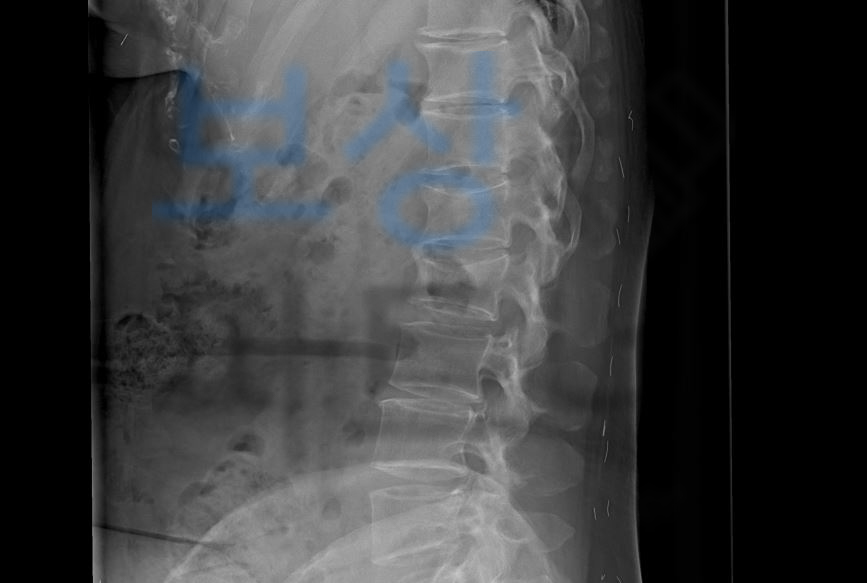

초기 내원한 병원에서 응급처치만 받고 더 큰 병원으로 전원한 의뢰인은 정확한 진단과 치료를 위해 정밀검사를 받게 되셨는데요, 그 결과,

Compression of L1, L2 body

즉 압박골절 요추 1번, 요추 2번 척추체 진단을 받으셨습니다. 위 사고로 TLSO 보조기라고 불리는 흉요추 허리 보조기를 착용하시며 최소 8주간은 요양하셔야 했는데요, 척추골절 겪으신 여러분들… 이미 아시겠지만 말이 8주이지… 최소 3개월간은 허리 보조기 착용하며 최대한 안정을 요하라는 소견을 받습니다.